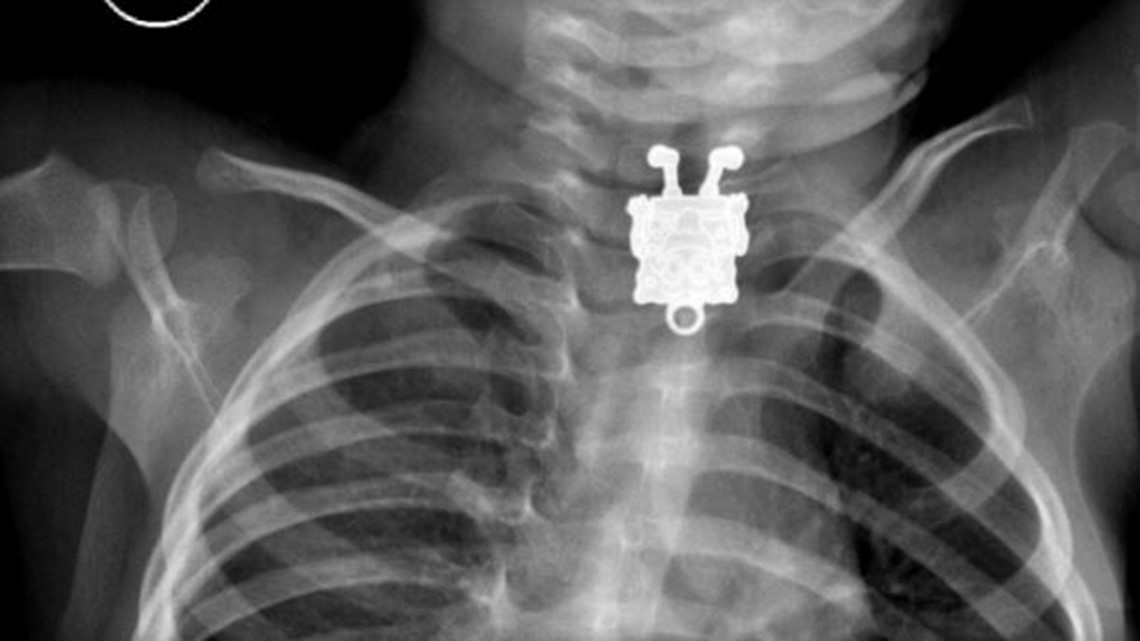

Ingested foreign body SpongeBob SquarePants Radiology Case Spongebob, X

XRay Photos Child Swallows SpongeBob SquarePants Spongebob X Ray We have a great online selection at the lowest prices with fast & free shipping on. Get the best deals for spongebob xray figure at ebay.com. Receiving the xxray plus treatment, explore the anatomy of the world’s most lovable. Spongebob squarepants series 04 (super edition) Upside down spongebob squarepants foreign body projecting over the thoracic inlet. Spongebob X Ray.

XRay Reveals SpongeBob SquarePants In A Toddler's Chest, Because Kids Are Terrifying Spongebob X Ray Get the best deals for spongebob xray figure at ebay.com. Upside down spongebob squarepants foreign body projecting over the thoracic inlet. Receiving the xxray plus treatment, explore the anatomy of the world’s most lovable. We have a great online selection at the lowest prices with fast & free shipping on. Spongebob squarepants series 04 (super edition) Spongebob X Ray.

SpongeBob Squarepants toy swallowed by toddler seen on XRay in his stomach SMILING Mirror Spongebob X Ray Get the best deals for spongebob xray figure at ebay.com. Spongebob squarepants series 04 (super edition) We have a great online selection at the lowest prices with fast & free shipping on. Receiving the xxray plus treatment, explore the anatomy of the world’s most lovable. Upside down spongebob squarepants foreign body projecting over the thoracic inlet. Spongebob X Ray.